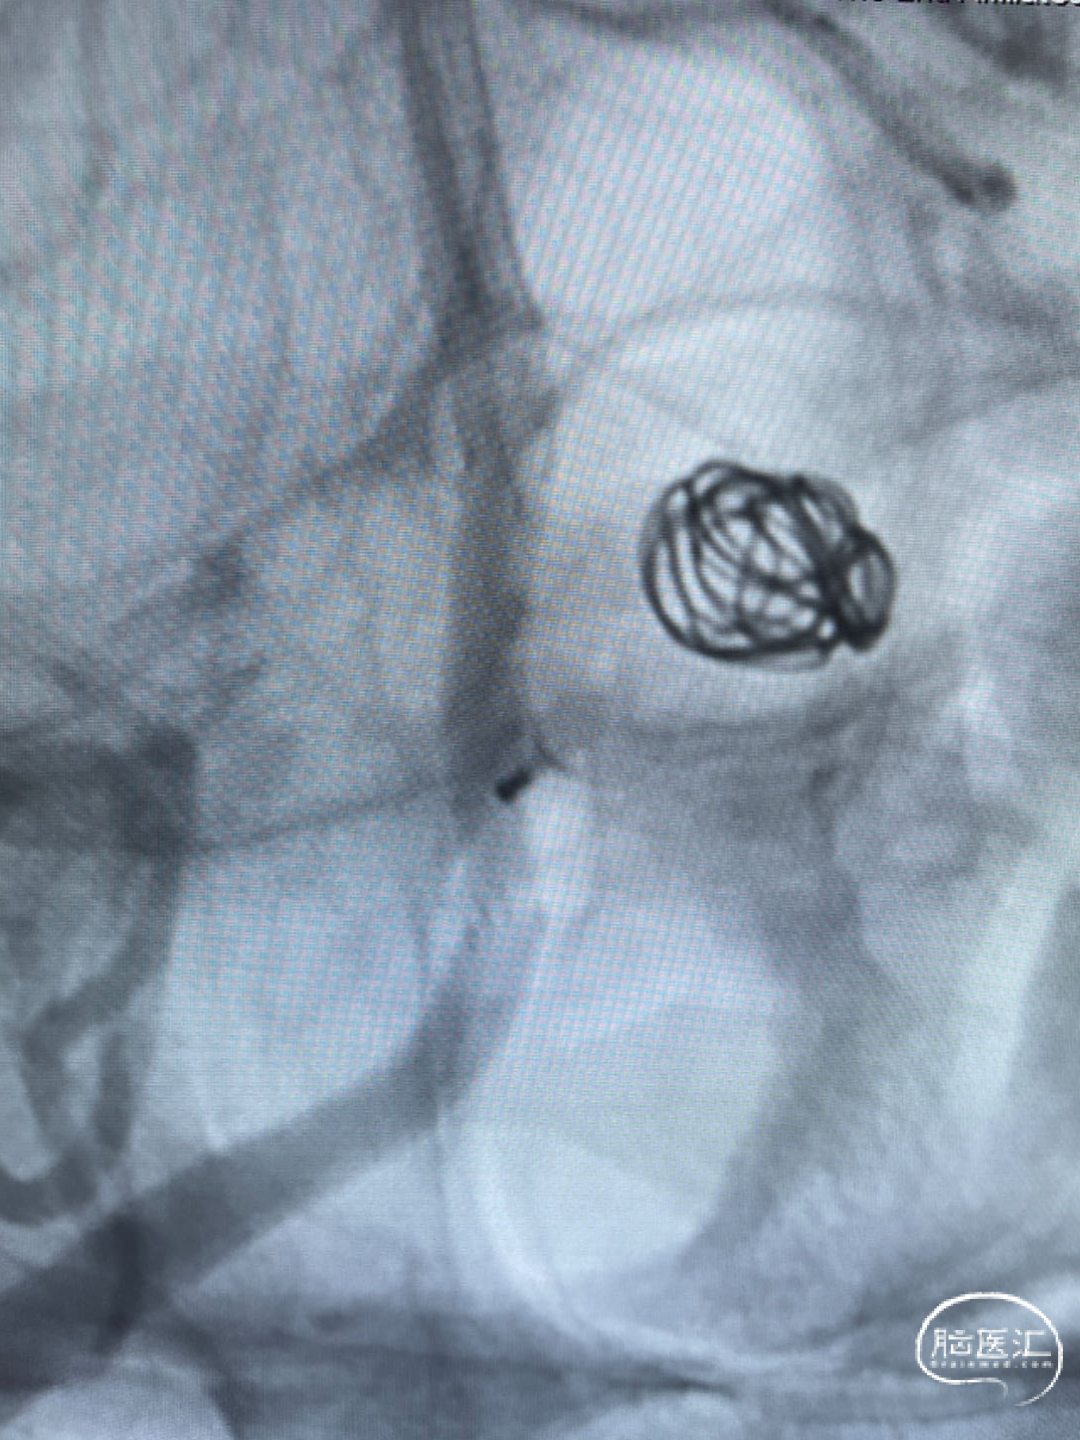

经测量可得动脉瘤宽度平均值为7.0mm,动脉瘤高度为7.4mm,最终选择WEB™ SL 9*6。

动脉瘤远端子囊先进行填圈,近端动脉瘤植入WEB™。

术后6个月影像提示血栓形成,动脉瘤完全闭塞,WEB™完全栓塞。